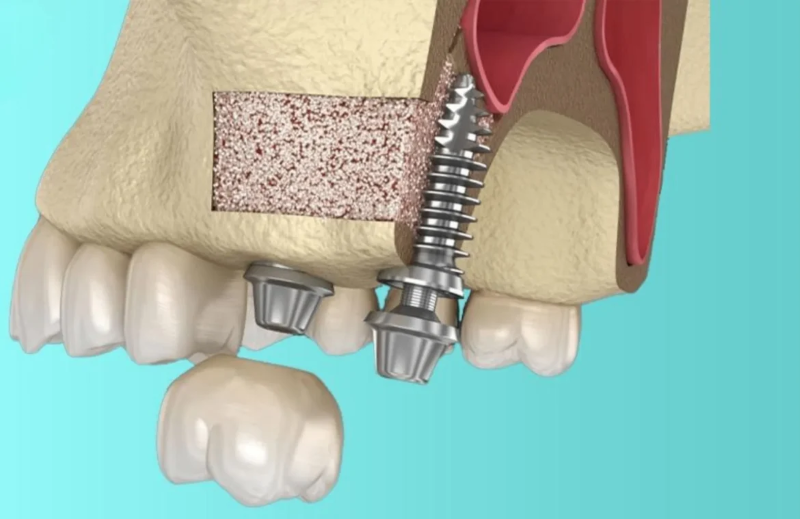

Thủng xoang hàm (Đối với hàm trên)

Đối với các trường hợp cấy ghép ở hàm trên, thủng xoang hàm là một biến chứng có thể xảy ra nếu trụ implant được cấy vào quá sâu. Khi điều này xảy ra, không chỉ gây ra khó khăn trong việc thực hiện thủ thuật mà còn có thể gây ra nhiễm trùng xoang, gây đau đớn cho bệnh nhân.

Bác sĩ cần có kiến thức vững vàng về giải phẫu vùng mặt và hàm để tránh biến chứng này. Việc chụp CT 3D trước khi phẫu thuật cũng là một biện pháp cần thiết để xác định đúng vị trí và chiều sâu của xoang hàm, giảm thiểu nguy cơ thủng xoang.

Trước khi tiến hành cấy ghép, việc thăm khám tổng quát là rất cần thiết để đánh giá tình trạng sức khỏe của bệnh nhân. Bác sĩ sẽ kiểm tra những yếu tố như sự chắc khỏe của xương hàm và tình trạng nướu. Chụp CT 3D cũng là bước quan trọng giúp bác sĩ có hình ảnh rõ ràng về cấu trúc răng miệng và xác định chính xác vị trí của trụ implant.

Nhờ vào công nghệ chụp CT 3D, bác sĩ có thể lên kế hoạch chi tiết cho ca phẫu thuật, từ đó giảm thiểu nguy cơ gặp phải biến chứng khi cấy ghép. Nếu có bất kỳ vấn đề nào phát hiện trong quá trình thăm khám, bác sĩ sẽ có thể đưa ra hướng điều trị hoặc phương án điều chỉnh phù hợp.